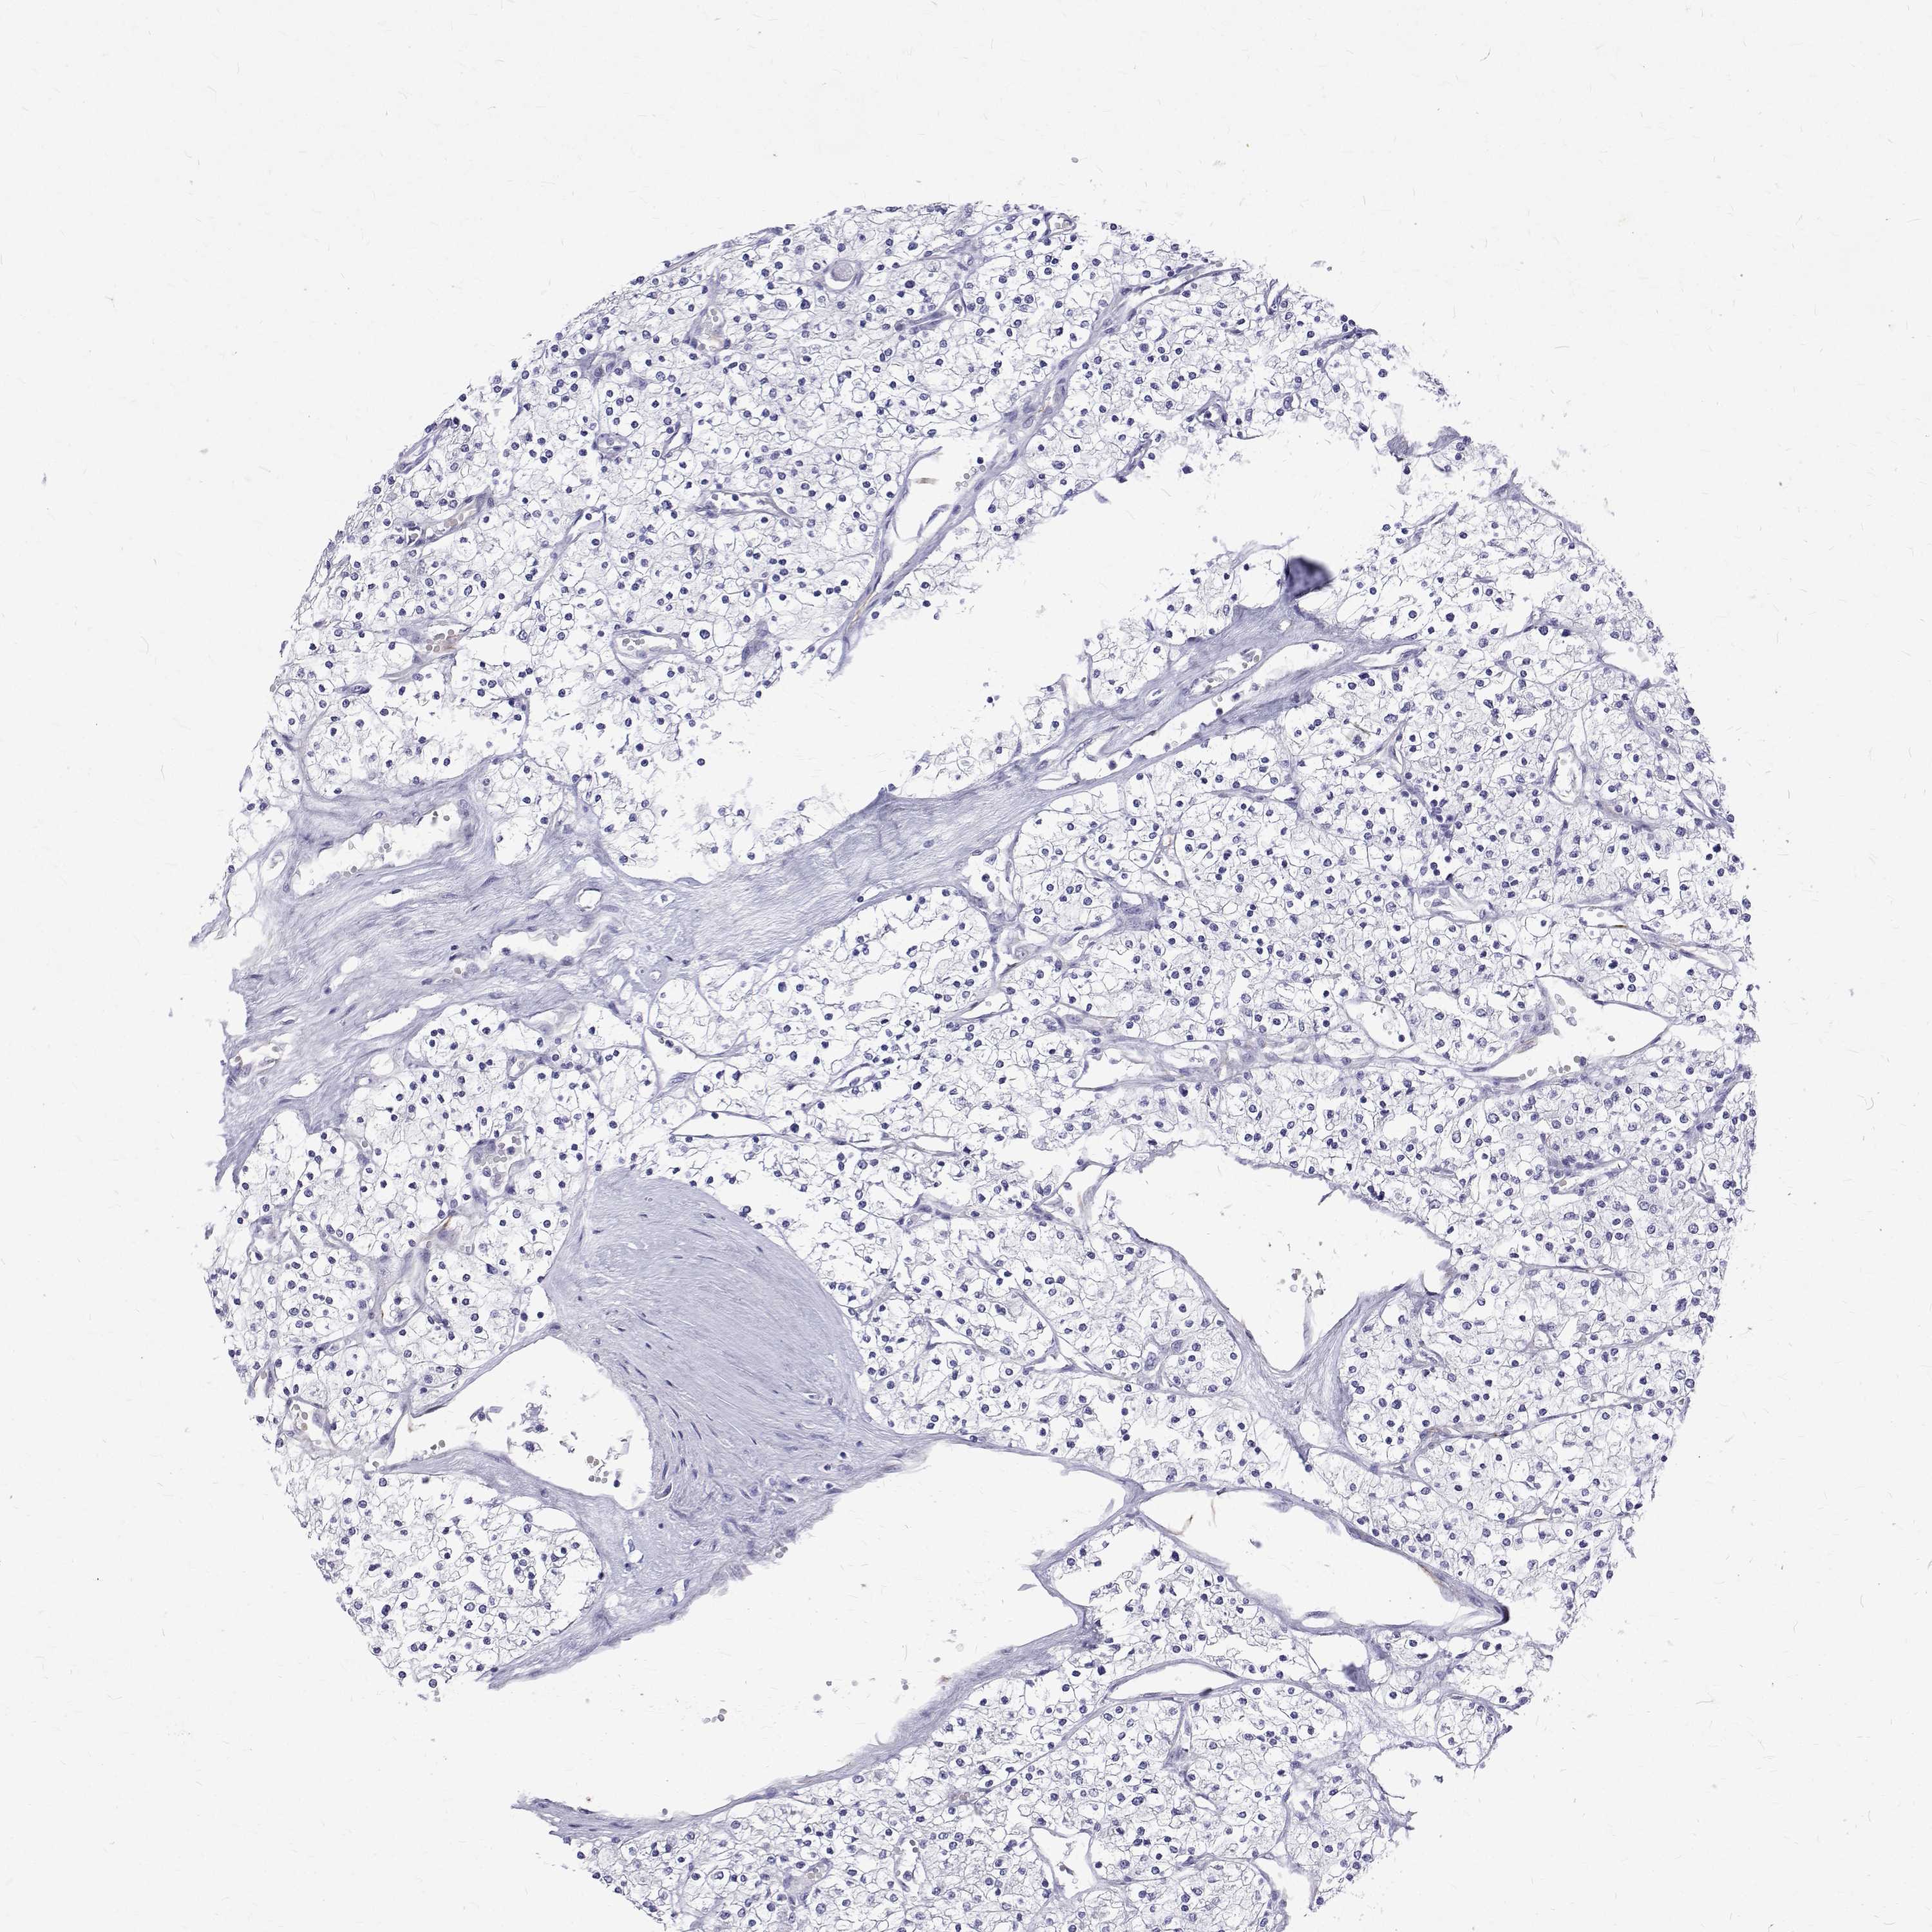

KIDNEY RENAL CLEAR CELL CARCINOMA (TCGA) - Interactive survival scatter ploti

The Survival Scatter plot shows the clinical status (i.e. dead or alive) for all individuals in the patient cohort, based on the same data that underlies the corresponding Kaplan-Meier plots. Patients that are alive at last time for follow-up are shown in blue and patients who have died during the study are shown in red.

The x-axis shows the expression levels (FPKM) of the investigated gene in the tumor tissue at the time of diagnosis. The y-axis shows the follow-up time after diagnosis (years). Both axes are complimented with kernel density curves demonstrating the data density over the axes. The top density plot shows the expression levels (FPKM) distribution among dead (red) and alive patients (blue). The right density plot shows the data density of the survived years of dead patients with high and low expression levels respectively, stratified using the cutoff indicated by the vertical dashed line through the Survival Scatter plot. This cutoff is automatically defined based on the FPKM cutoff that minimizes the p-score. The cutoff can be changed by dragging the vertical line or by entering a cutoff value in the square labeled "Current cut-off".

Under the Survival Scatter plot the p-score landscape (black curve; left axis) is shown together with dead median separation (red curve; right axis). Dead median separation is the difference in median mRNA expression between patients who have died with high and low expression, respectively. It is calculated as follows: median FPKM expression of dead patients with high expression - median FPKM expression of dead patients with low expression. This is intended to aid the user in visually exploring custom cutoffs and the associated p-scores and dead median separation.

Individual patient data is displayed and can be filtered by clicking on one or more of the category buttons on the top of the page. Categories describing expression level and patient information include: high, low, alive, dead, female, male and tumor stages. The scale of the x-axis can be toggled between linear and log-scale by clicking on the "x log" button. Mouse-over function shows TCGA ID, patient information and mRNA expression (FPKM) for each patient.

& Survival analysisi

Kaplan-Meier plots summarize results from analysis of correlation between mRNA expression level and patient survival. Patients were divided based on level of expression into one of the two groups "low" (under cut off) or "high" (over cut off). X-axis shows time for survival (years) and y-axis shows the probability of survival, where 1.0 corresponds to 100 percent.

Survival analysis data not available.

TCGA RNA samplesi

RNA-seq data is reported as average FPKM (number Fragments Per Kilobase of exon per Million reads), generated by the The Cancer Genome Atlas (TCGA) .

Normal distribution across the dataset is visualized with box plots, shown as median and 25th and 75th percentiles. Points are displayed as outliers if they are above or below 1.5 times the interquartile range. FPKM values of the individual samples are presented next to the box plot.

Average pTPM 0.0

Number of samples 521